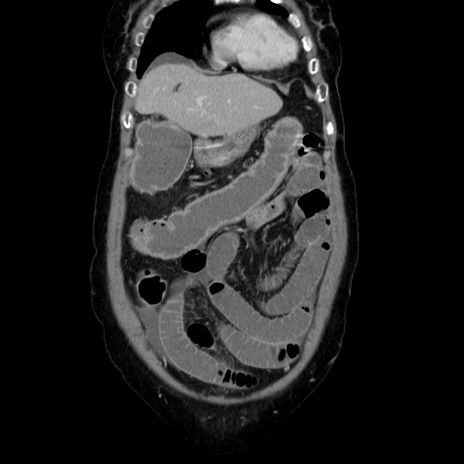

症例5(冠状断像)

【症例】70歳代女性

【主訴】お腹が張る

【現病歴】1週間くらい前から腹部膨満の自覚あり。昨日夜から増悪したため、本日救急外来受診。

【身体所見】意識清明、BT 36.5℃、BP 165/106mmHg、HR 80bpm、SpO2 98%、腹部:膨満、軟、自発痛・圧痛なし、触診にて不快感あり、腸蠕動音:減弱

【データ】WBC 12600、CRP 1.04